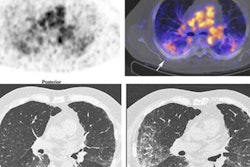

Comparatively, after five runs, their method produced consistent Zr-89 DFOSq-Durvalumab radiotracer yields of 75% and an automatic process time of 40 minutes, according to the findings. In addition, the group tested the radiotracer in mice, with Zr-89 DFOSq-Durvalumab showing excellent ability on PET imaging to detect cancer.